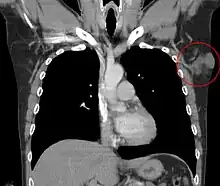

Distant hematogenous metastases are extremely rare.[34] Metastases to regional lymph nodes are rarer and are most likely in patients who have had multiple local recurrences after inadequate surgical resection.[35] Repeatedly recurring tumors have an increased risk for transformation into a more malignant form (DFSP-FS). The lungs are most frequently affected, but metastases to the brain,[36] bone,[37] and other soft tissues are reported.